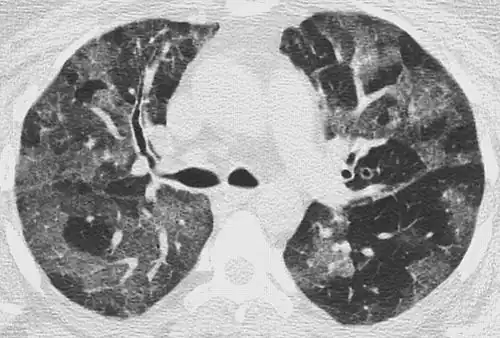

CT showing diffuse ground-glass opacities in periphery of both lungs in patient with COVID-19.

Ground-glass opacity is among the most common imaging findings in patients with confirmed COVID-19.[16][17] One systematic review found that among patients with COVID-19 and abnormal lung findings on CT, greater than 80% had GGOs, with greater than 50% having mixed GGOs and consolidation.[16] GGOs with mixed consolidation has most often been found in elderly populations.[18]

Several studies have described a pattern among initial, intermediate, and hospital discharge imaging findings in the disease course of COVID-19. Most commonly, initial CT imaging reveals bilateral GGOs at the periphery of the lungs. During initial stages, this is most often found in the lower lobes, although involvement of the upper lobes and right middle lobe has also been reported early in the disease course.[16][18] This is in contrast to the two similar coronaviruses, SARS and MERS, which more commonly involve only one lung on initial imaging.[19][20] As the COVID-19 infection progresses, GGOs typically become more diffuse and often progress to consolidation.[11][18] This is sometimes accompanied by the development of a crazy paving pattern and interlobular septal thickening.[18] In many cases the most severe pulmonary CT abnormalities occurred within 2 weeks after symptoms began.[17] At this point, many individuals begin showing resolution of consolidation and GGOs as symptoms improve. However, some patients have worsening symptoms and imaging findings, with further increase in septal thickening, GGOs, and consolidation. These patients may develop lung "white-out" with progression to acute respiratory distress syndrome (ARDS) requiring treatment escalation.[17][21]

Preliminary reports have shown many patients have residual GGOs at time of discharge from the hospital. Due to the novelty of COVID-19, large studies investigating the long-term pulmonary CT changes have yet to be completed. However, long-term pulmonary changes have been seen in patients after recovery from SARS and MERS, suggesting the possibility of similar long-term complications in patients who have recovered from acute COVID-19 infection.[22]